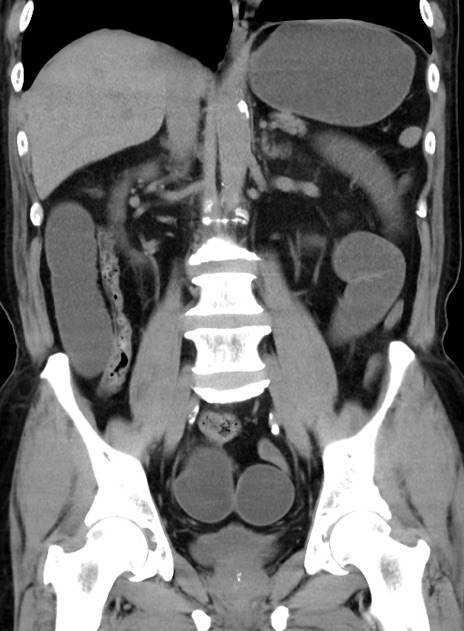

症例38(冠状断像)

【症例】70歳代 男性

【主訴】腹痛・嘔吐

【現病歴】昨晩より、嘔吐・腹痛あり。今朝になっても嘔吐あり。来院。

【既往歴】心臓バイパス手術、開腹胆摘、腸閉塞

【身体所見】BP 107/71mmHg、HR 116/min、腹部:平坦、軟、下腹部に軽度圧痛あり。反跳痛なし。

【データ】WBC 15100、CRP 0.32